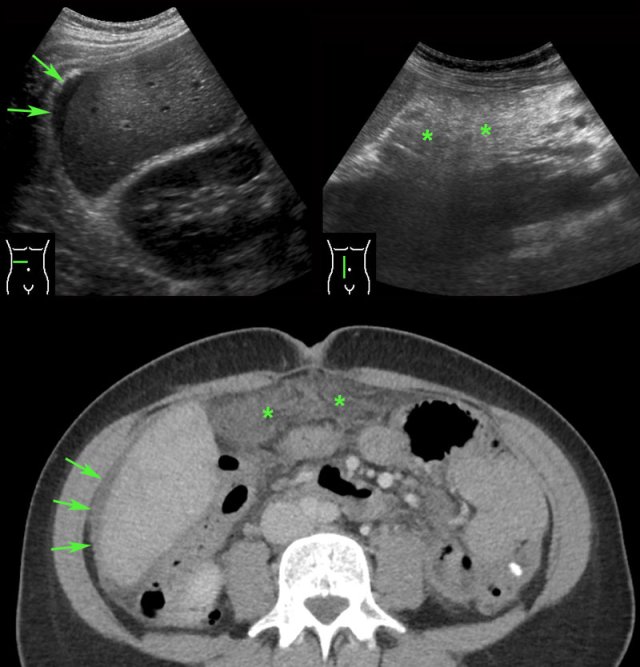

case 1

Four days after delivery this young woman developed

pain in the RLQ and a CRP of 125.

At the spot of maximum pain an ill-defined, solid,

tubular, hypoechoic structure (*) was seen, surrounded by hyperechoic, non-compressible,

inflamed fat (arrowheads).

CT confirmed an ovarian vein thrombosis. The surrounding

fat-stranding suggested a concomitant, phlebitis-component.

Complete recovery with antibiotics and anticoagulant therapy.

case 2

This patient presented with RLQ pain 5 days after the procedure.

US demonstrated a thrombus in the right ovarian vein, there was no clear phlebitis

component.

CT confirmed a thrombus in the right ovarian vein, without

any fat stranding.

CRP remained low.

Complete cure with only anticoagulant therapy.